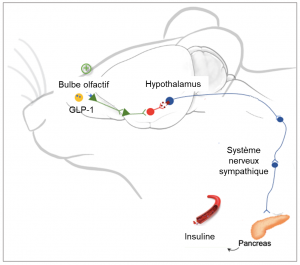

Lorsque l’on mange, le système gastro-intestinal sécrète une hormone appelée glucagon like peptide-1 (GLP-1). Le GLP-1 circulant dans le sang stimule à son tour la sécrétion d’insuline par le pancréas de façon à assimiler les divers sucres ingérés. Mais le GLP-1, utilisée par ailleurs comme antidiabétique, est également produit localement dans le cerveau au niveau du bulbe olfactif, lorsque ce dernier détecte une odeur. Les chercheurs de l’équipe Reglys ont mis en évidence le circuit par lequel le GLP-1, sécrétée par le bulbe olfactif, influence l’activité du pancréas et stimule la sécrétion d’insuline. Les résultats des travaux montrent que le GLP-1 sécrété par le bulbe olfactif ne passe pas dans la circulation sanguine mais agit à courte distance pour contrôler l’hypothalamus non loin de là. Lorsque le signal envoyé par le GLP-1 est détecté, L’hypothalamus entre alors en action en envoyant des signaux nerveux au pancréas, via le système nerveux sympathique, qui déclenchent alors la sécrétion d’insuline.

Le GLP-1 produit dans le bulbe olfactif envoie un signal vers l’hypothalamus. L’hypothalamus contrôle l’activité nerveuse sympathique qui contrôle à son tour la sécrétion d’insuline. Lorsque les neurones du GLP-1 s’activent pendant un repas la sécrétion d’insuline est stimulée via ce réseau neuronal.

Actuellement, des analogues de synthèse du GLP-1 constituent une nouvelle génération d’antidiabétiques.

L’équipe de recherche Reglys, souhaite poursuivre ses recherches en approfondissant l’étude du mode d’action de ces molécules dans le bulbe olfactif et tester notamment leur administration par voie intranasale sur la sécrétion d’insuline ce qui ouvrirait un nouveau champ de recherche dans le cadre du traitement du diabète.